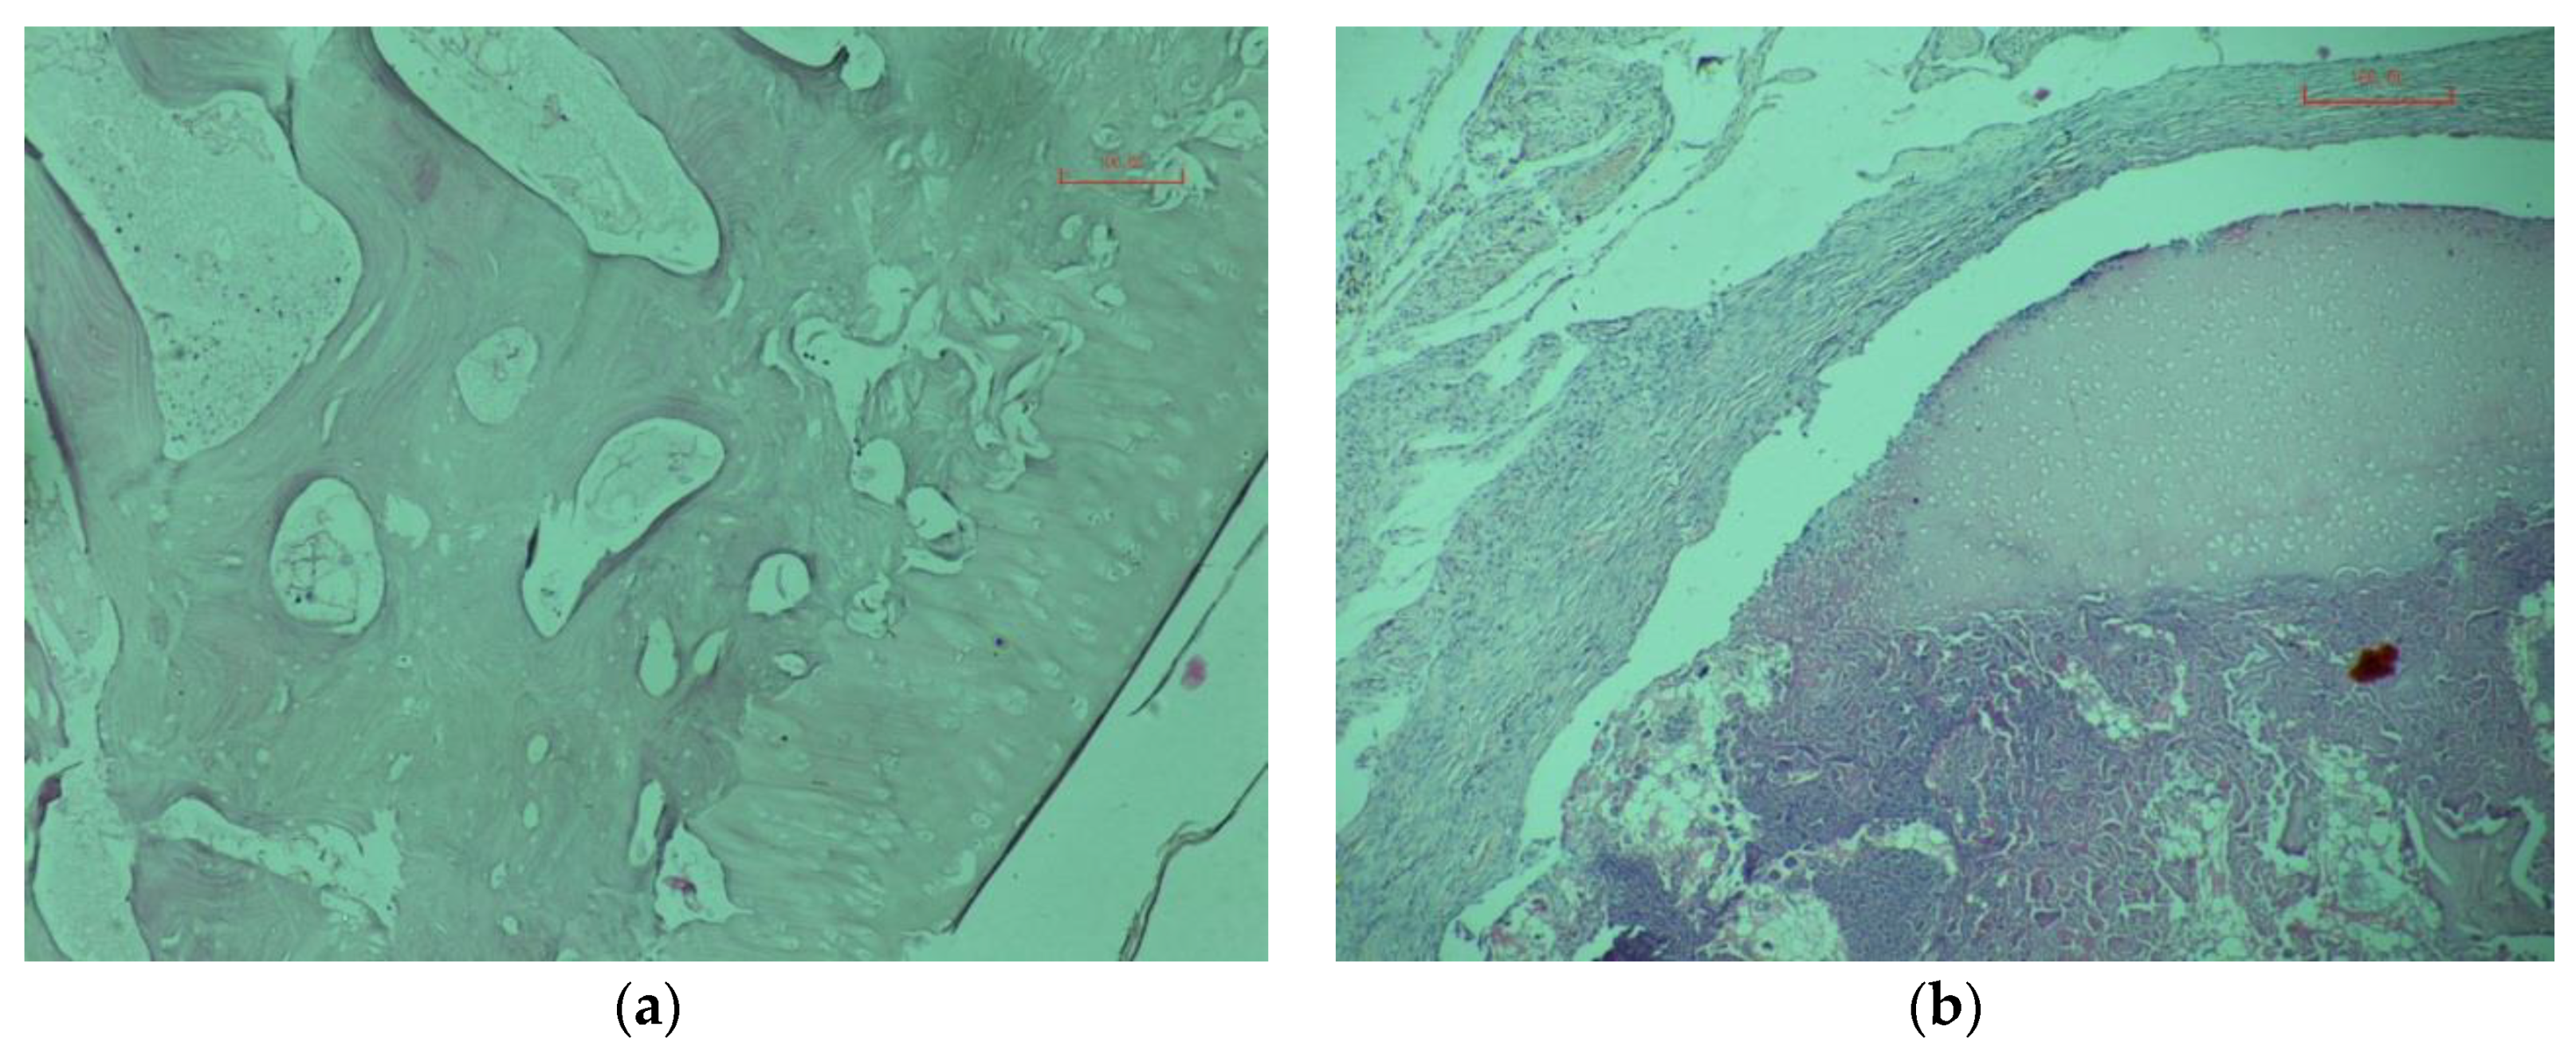

On the 45th day after transplantation in animals of the control and experimental groups in the transplanted bones, the cells are not determined (see Figure 7a).

Figure 7. Micrograph of bone X400: The 110 days after transplantation, control animal (a); 110 days after transplantation, experienced animal (b).